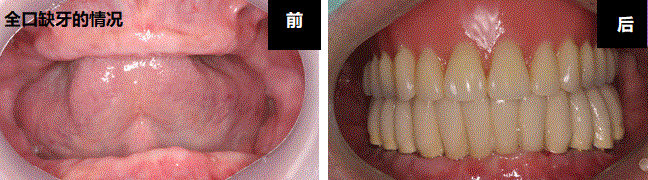

牙齿完全没有的时候也使用种植牙可以离开假牙。使用7~12个左右的种植牙制作口康假体,可以跟正常牙齿一样使用。咬的力也比使用假牙的时候强,而且不用带假牙的优点也有。通过PARK AVENUE的技术秘诀细心地考虑牙齿的状态和骨头吸引程度植立正确和安全的种植牙。

2. 假牙性种植牙

全口缺牙的话特别通过种植牙制作比基准使用的假牙方便和性能好的假牙。颚骨前面部分2~4个左右种植牙植立后安装假牙。